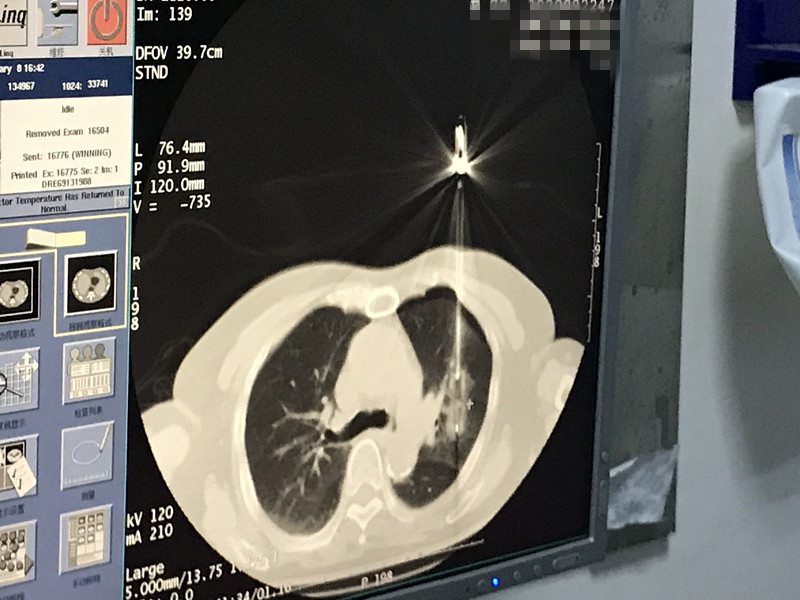

下一篇:2021年1月份肺部氩氦刀手术